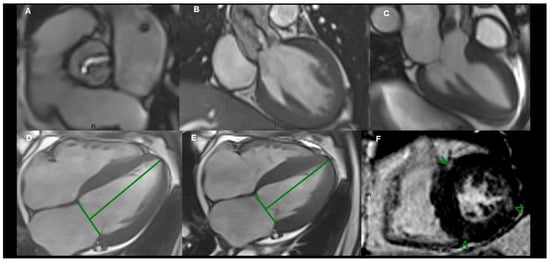

2.5. Cardiac Magnetic Resonance Imaging